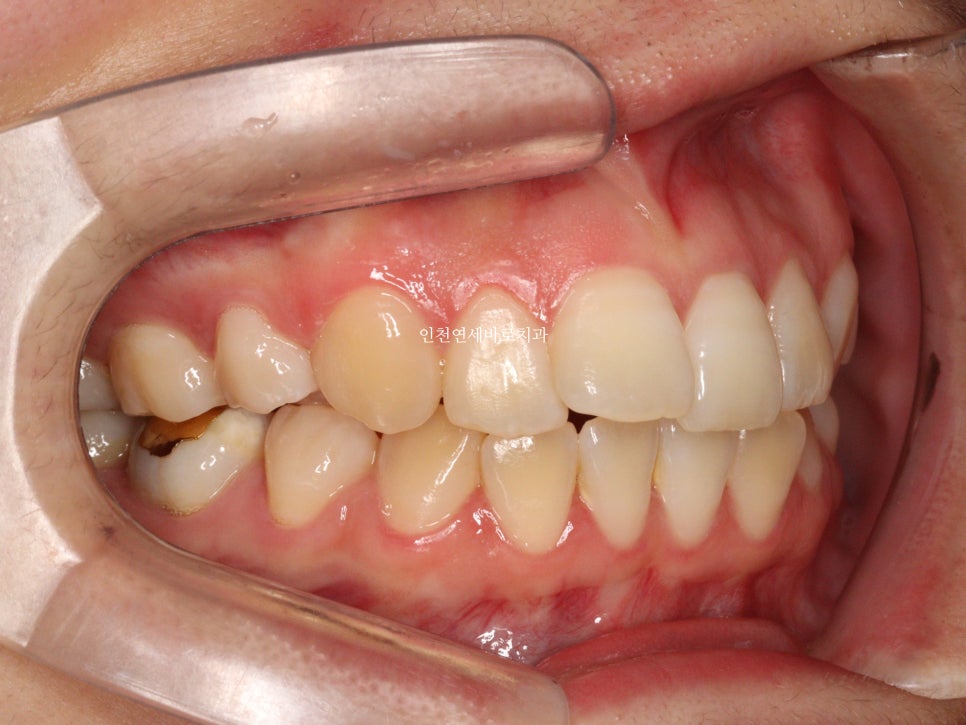

오늘은 교정이 끝난지 오래되어 재교정을 하고 싶어 내원했던 환자분 이야기 입니다.

예전에 중학생때 발치교정치료를 받았다고 합니다.

환자분의 나이는 이제 30대

약 15년만에 다시 교정치료를 결심하셨다고 합니다.

결혼을 앞둔 분이었고

앞니하나가 많이 틀어졌는데 점점 틀어진다고 하셨습니다.

철사 유지장치를 붙여놨었는데 오래전에 탈락 하고 다시 붙이지 않으셨다고 합니다.

변화모습입니다.

약 3개월의 변화모습입니다.